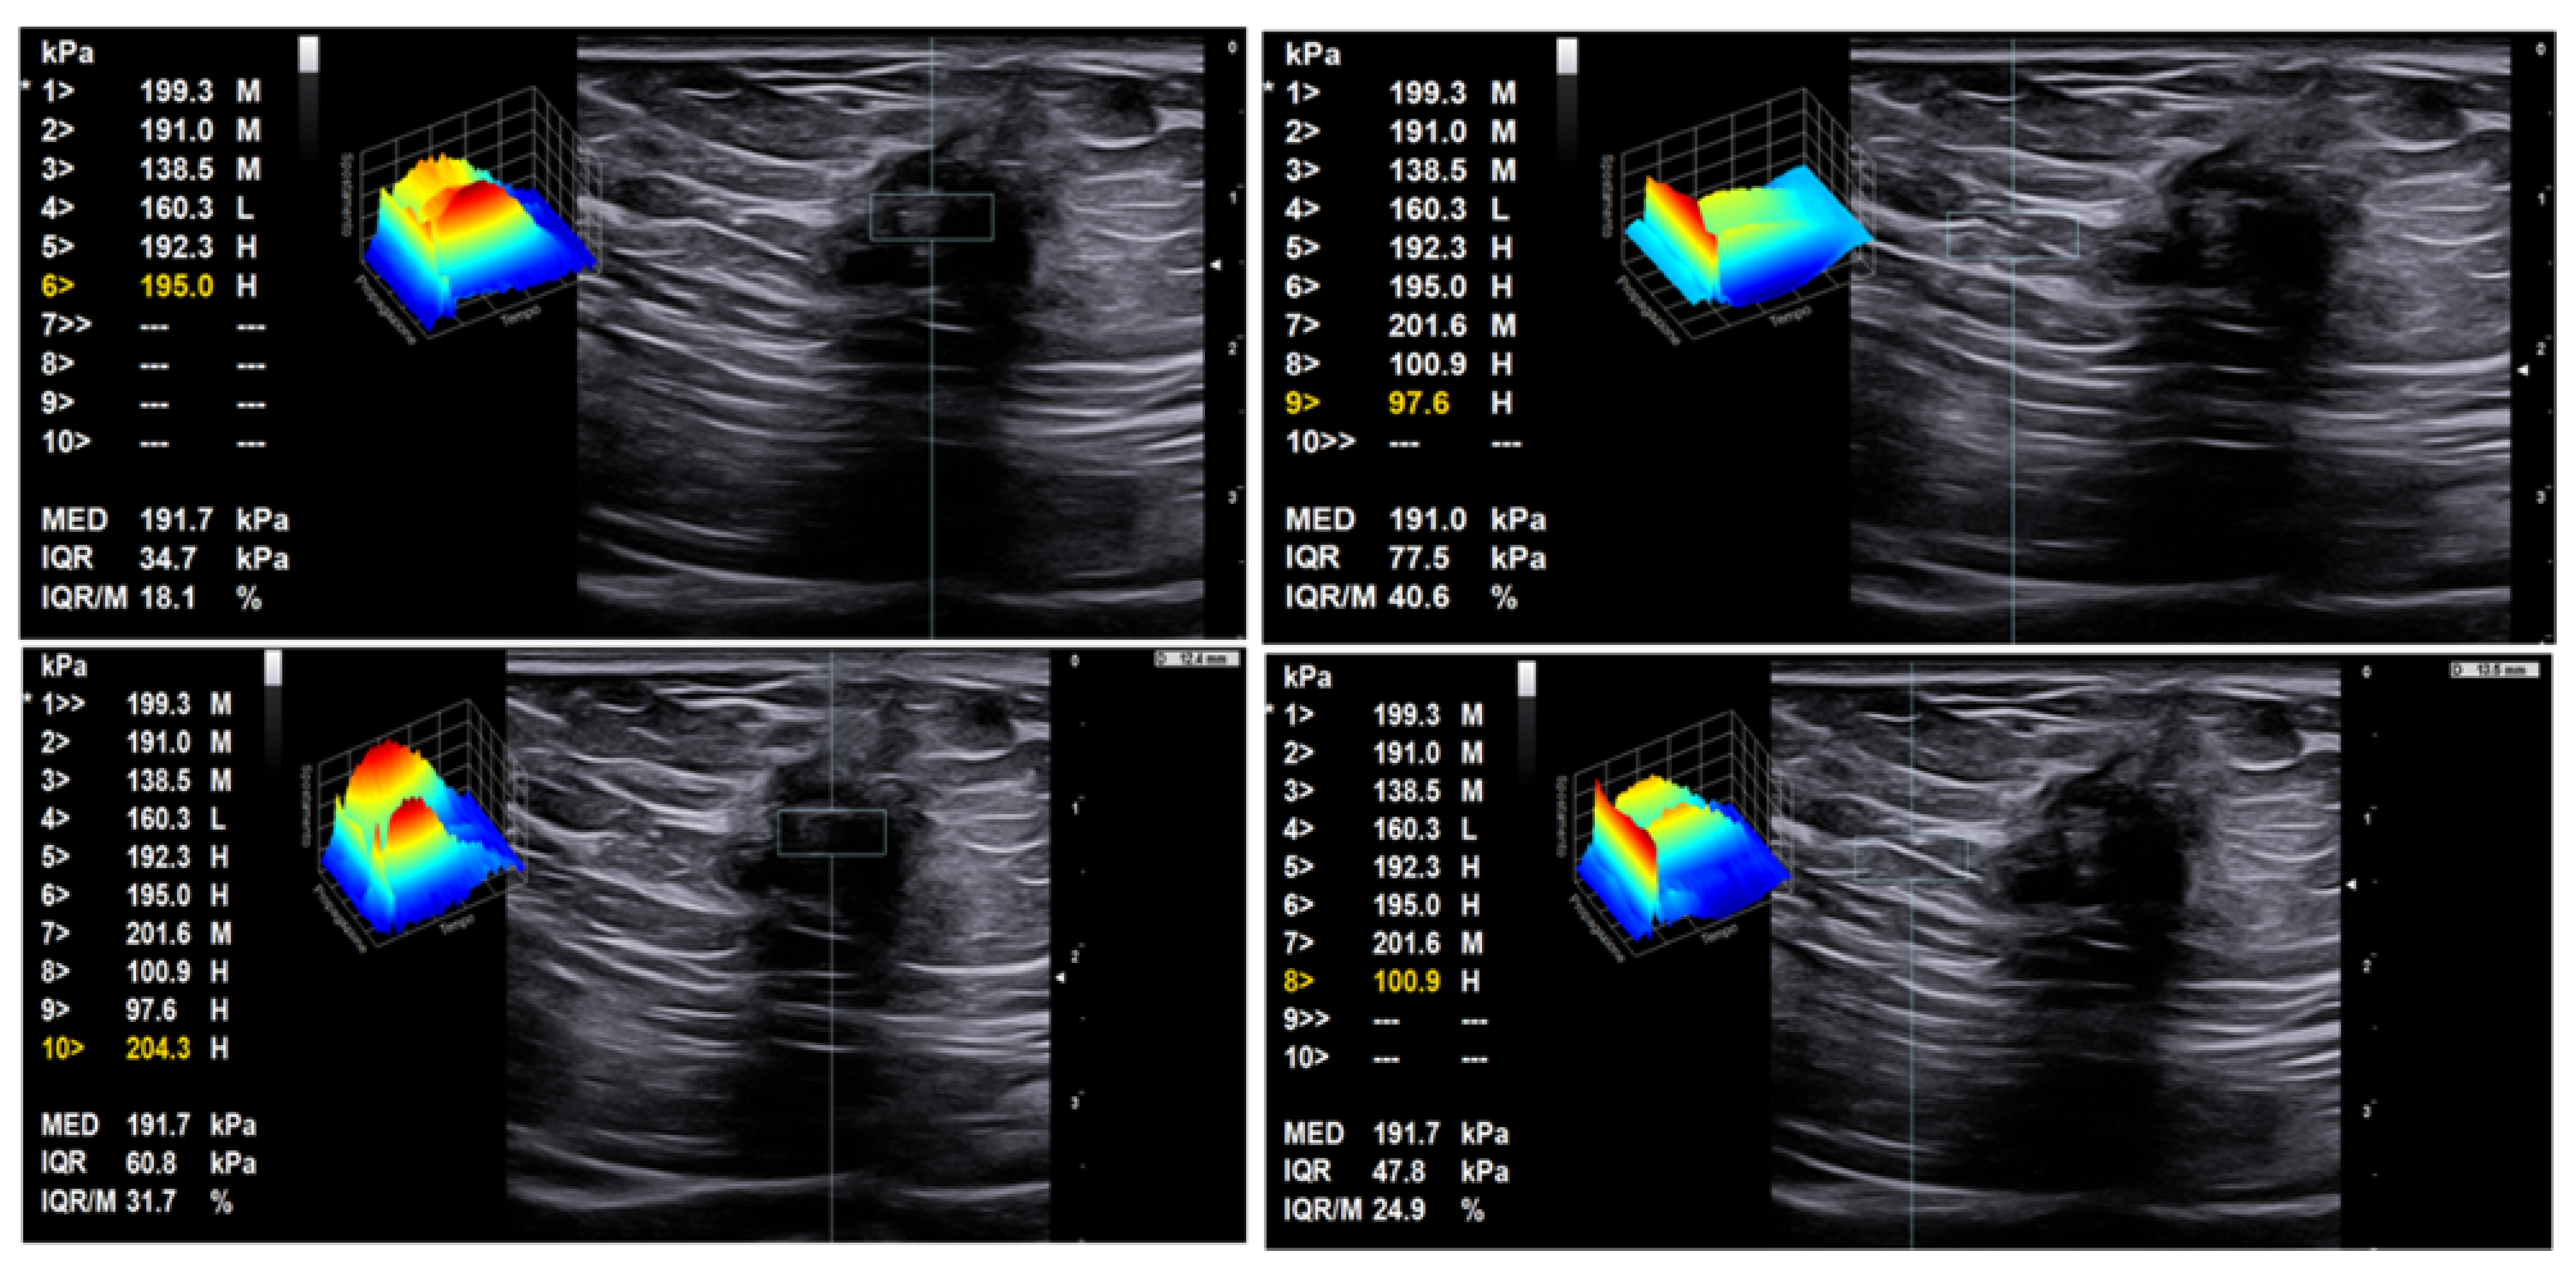

- Xie, M.; Zhang, X.; Zhan, J.; Ren, Y.; Wang, W. Potential role of strain elastography for detection of the extent of large-scar endometriosis. J. Ultrasound Med. 2013, 32, 1635–1642. [Google Scholar] [CrossRef]